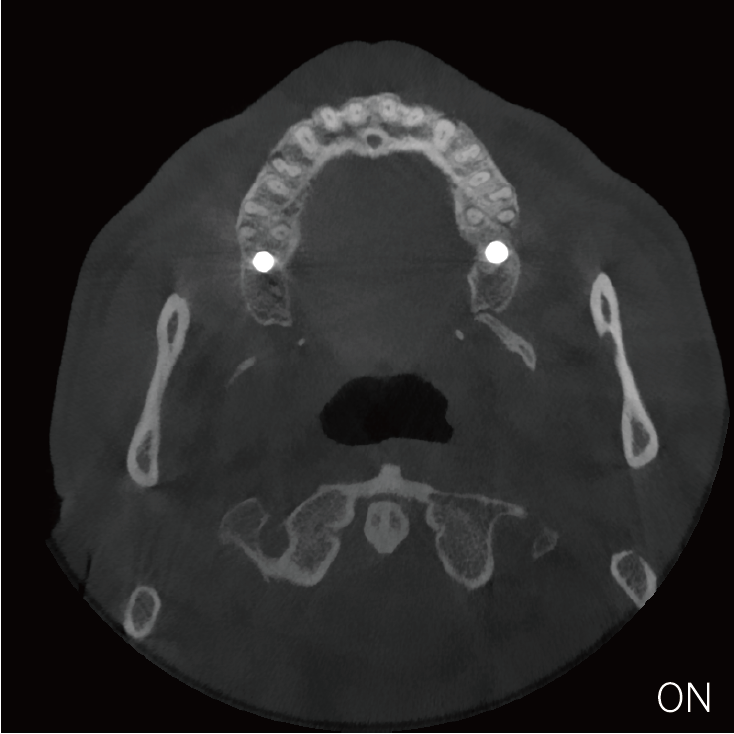

超能去伪 至臻影像

支持局部超清三维显示

可根据临床需求任意调整成像区域大小实现局部超清三维显示